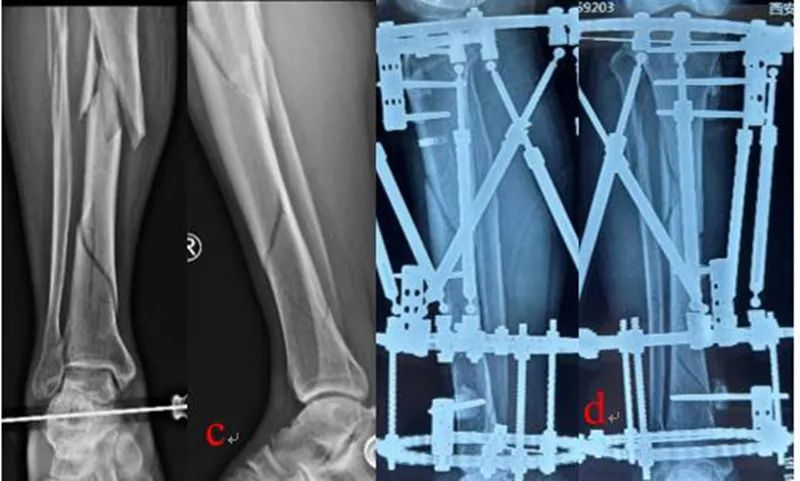

利用骨科外固定架(QF)和数字六轴外架(QSF)治疗胫骨骨折,获得良好的临床疗效.骨科外固定架具有自动复位骨折功能,4根螺纹连接杆与骨的轴线平行,通过旋拧调节螺母,调节两个固定环之间的距离,实现对骨折断端轴向应力的调节和固定方式的转换,早期坚强固定,中期加压固定,后期弹性固定。复位过程无需透视,不依赖医生经验,手术时间短,可以不用麻醉,术后即可完全负重下地行走,复位精确,固定合理,操作简便。数字六轴外架QSF配套软件基于CT数据,与国际同类产品比较,复位精确,固定牢靠,操作简便,学习曲线短。

图2:QSF治疗胫腓骨骨折